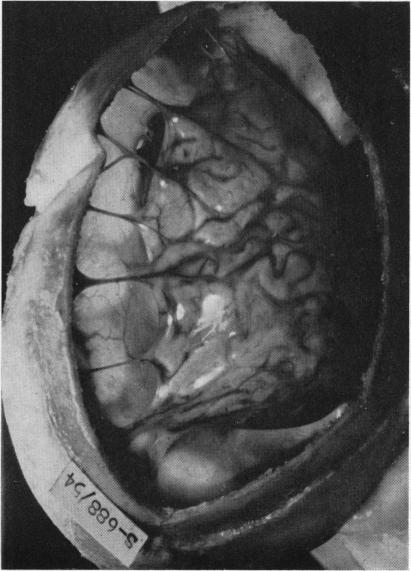

HERZBERGER E, ROTEM Y, BRAHAM J

Arch Dis Child. 1956 Feb;31(155):44-50. doi: 10.1136/adc.31.155.44.